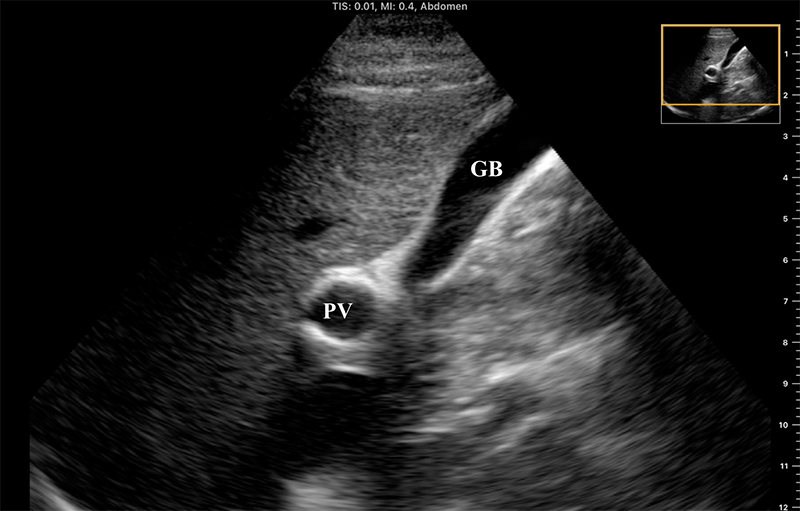

- The portal vein may also be located in short axis by tracing the gallbladder down its long axis to the neck, forming the “exclamation point”

Figure 9. “Exclamation point” revealing the gallbladder (GB) in long axis with the bright-walled portal vein (PV) in short axis.

- The larger, bright-walled portal vein will often be seen with the two smaller structures of the portal triad in the same cross section, a hepatic arterial branch and common bile duct.

Figure 10. The portal triad seen in short axis. The portal vein (PV) is the largest, while the hepatic artery and bile duct (arrows) are much smaller and often indistinguishable without color Doppler.